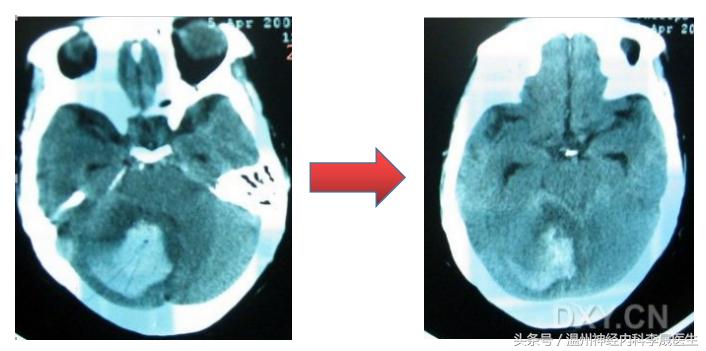

2、小脑出血,易形成脑疝

出血量≥10ml,或直径≥3cm,或合并脑积水,应尽快手术治疗。

3.预后判断

脑出血预后的三个重要预测因子就是血肿大小,出血位置,患者入院时的意识状态(GCS评分)

1)出血量大,全身情况差者,死亡率高。最大直径大于3cm的血肿死亡率较高。

2)脑干出血病死率达70%,大脑半球出血约20%,总的病死率为30-40%。

3)存活者残废率达70%